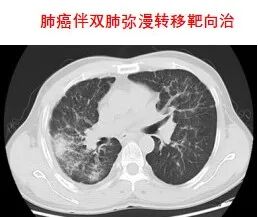

放射治疗是利用高能放射线消灭肿瘤的原发灶或转移灶的一种局部治疗方法。是治疗恶性肿瘤的三大手段之一,具有无创、副作用小、适应范围广、肿瘤局部控制率高等优点。适应症:全身各部位早、中、晚期恶性肿瘤。